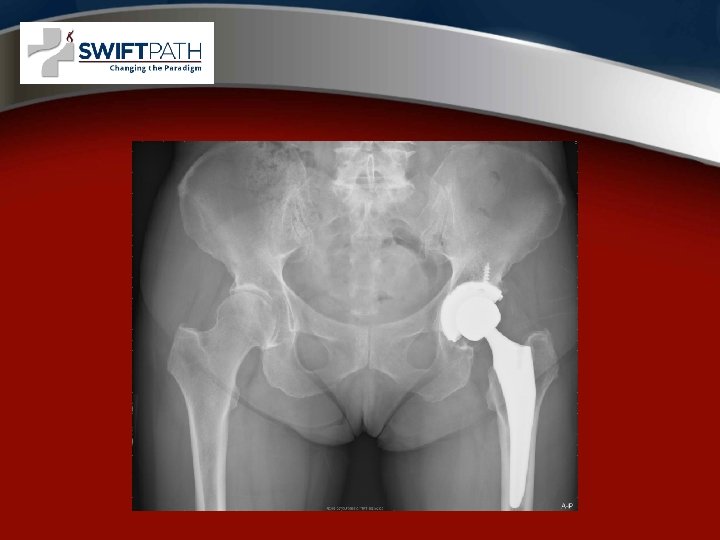

Xrays after hip Replacement • Metal stem and cup

The fundamental problem in hip replacement design was bearing surface wear, leading to loosening • • Improvements included Better plastic or polyethylene Ceramic bearings Metal on metal bearing

Anterior approach No Muscles or tendons cut

• • Anterior vs posterior Anterior Approach Less pain in the first 2 weeks. Return to work on average 2 weeks sooner. More blood loss, need special training and the hana table. Lower dislocation rate. Larger area of numbness around the incision. Not possible with Obesity and some pelvic anatomy. No long term functional or survival differences.